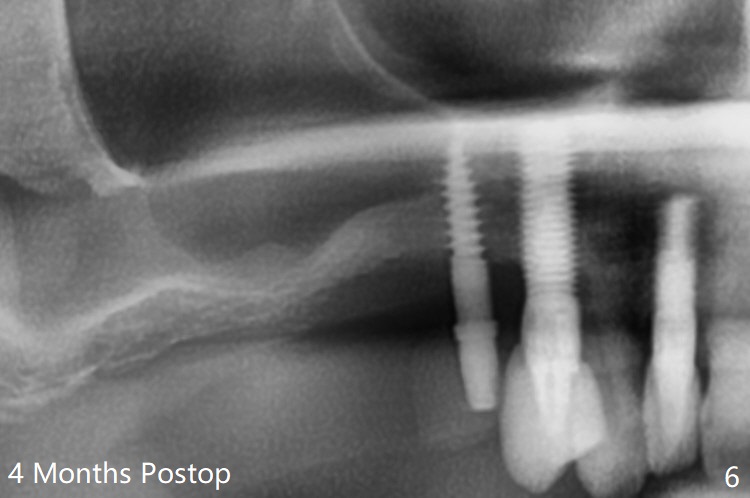

术前检查发现右上6颊侧牙龈沟有脓性分泌物(图一),翻瓣显示骨质吸收(图二),曾经植骨三次,只好去骨,取出植体,远中颊侧轻度上颌窦穿孔(图三:>),塞入小块PRF膜后,患处放置粘性骨粉,覆盖两块PRF膜和一片GEM Cap(9-12月吸收膜),三者近中一端有一个洞,挂在5基台上固定。术后即刻根尖片显示骨粉充填穿孔(图四:>),6缺失区以及5远中(*)。术后第二天牙周敷料脱落,术后16天病人回来,要求剪除缝线,伤口尚未关闭,下面黄色骨粉好像挺牢靠;为了减少继续骨粉丧失,使用树脂敷料(图五)。术后四周敷料稳定,牙龈健康,但是不放心下面伤口愈合,暂时没有撤去敷料。术后四个月骨质高度不足(图六至八),上颌窦膜薄,提升不容易,可放置5x7.3毫米植体(IBS),PRF。Return to No Caries 4 Placement 种植杂谈 Xin Wei, DDS, PhD, MS 1st edition 01/26/2021, last revision 07/30/2021